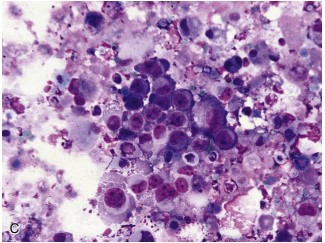

Diagnosing Intrapulmonary Tumors

EUS and EBUS are not only limited to nodal staging but can also diagnose intrapulmonary tumors, especially those adjacent to the esophagus and major airways. This capability extends the applicability of endosonography in lung cancer diagnosis and treatment.